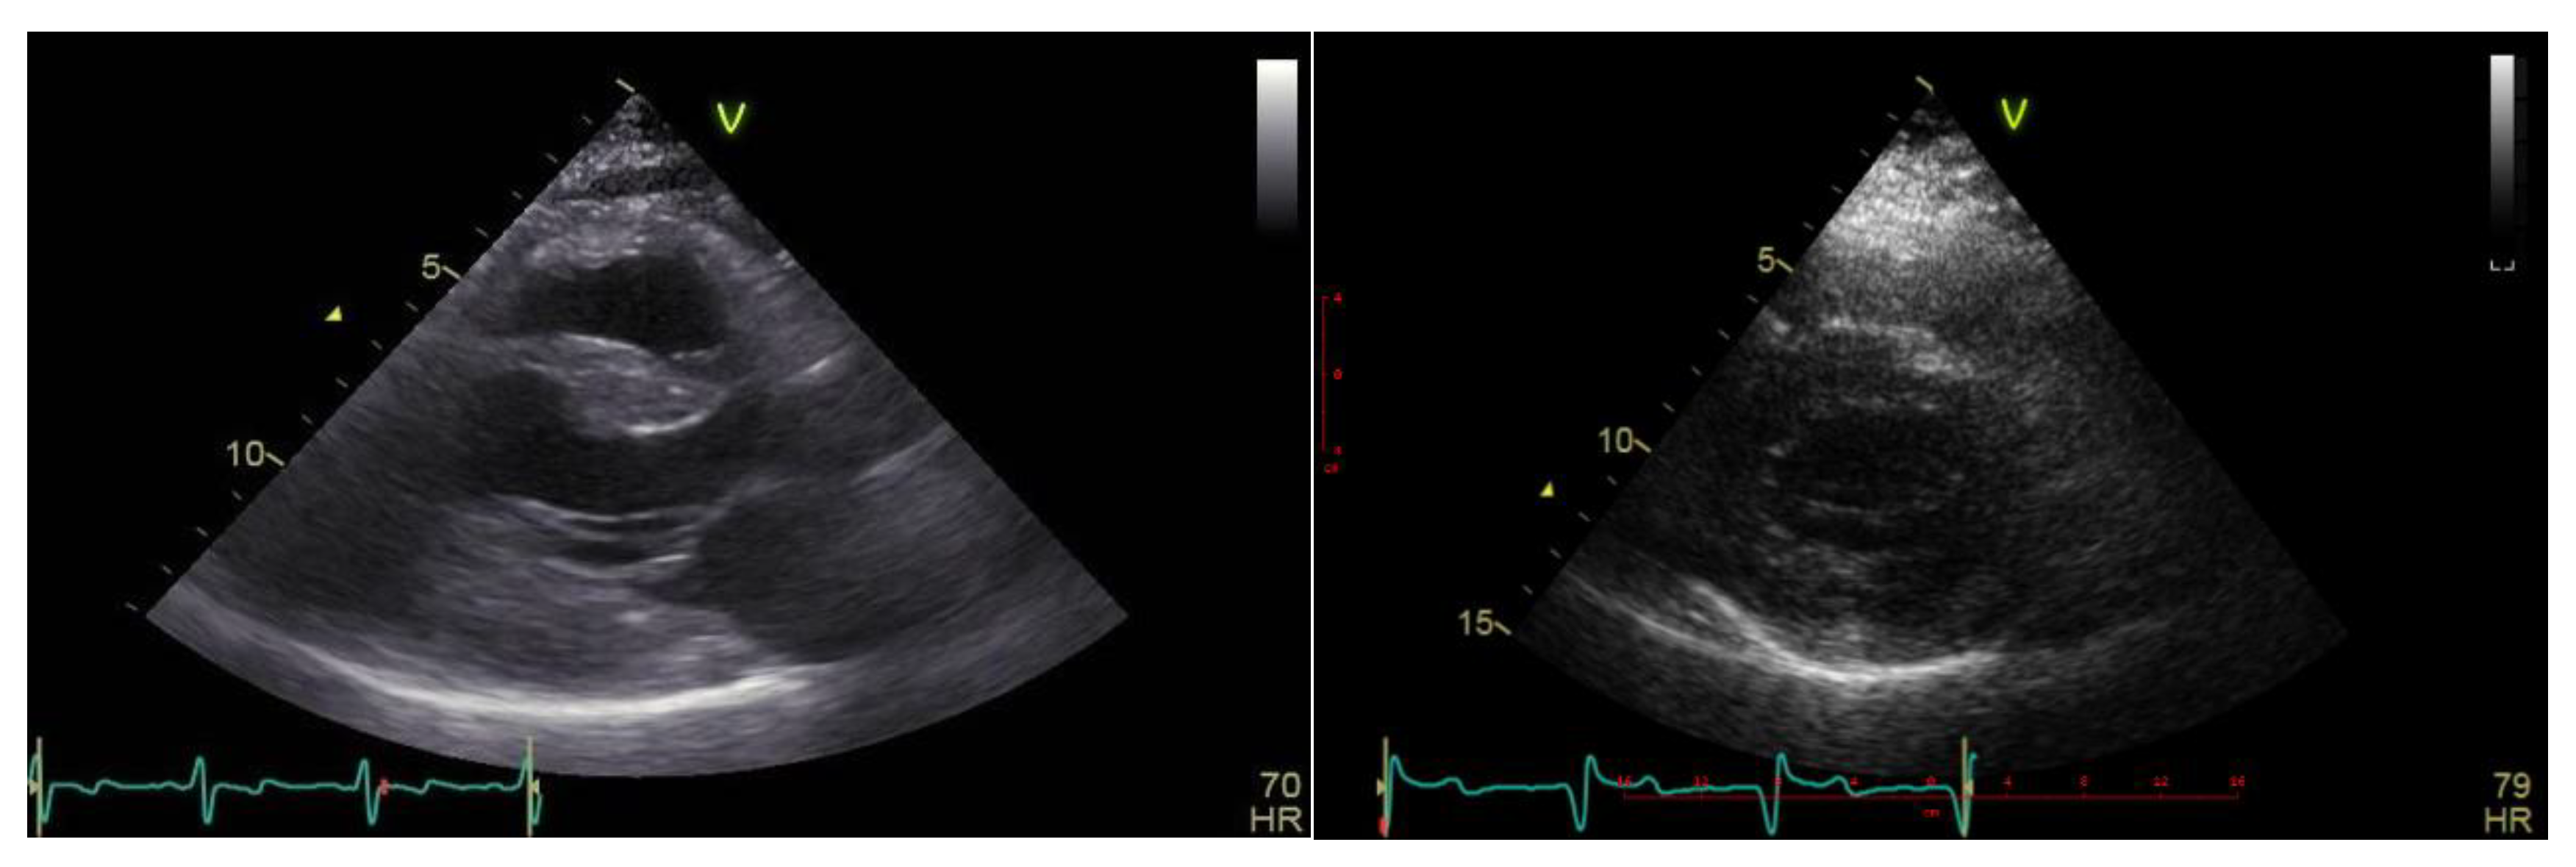

Case description